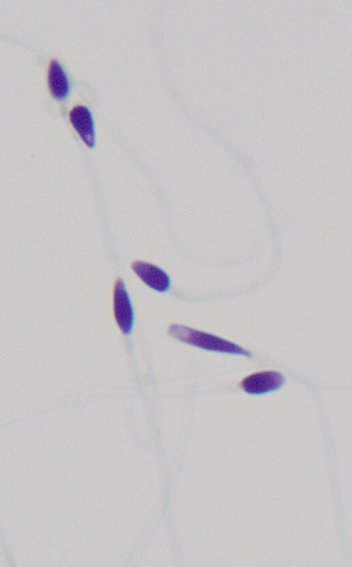

一条精子,全长50μm(1cm=10000μm),由三大主要部分组成:头部、颈部和尾部。

一个健康的高颜值精子,应该由一个完美、光滑的椭圆形头部和一条长而飘逸的尾部组成。

头部畸形精子

锥 形 头 精 子

梨形头精子